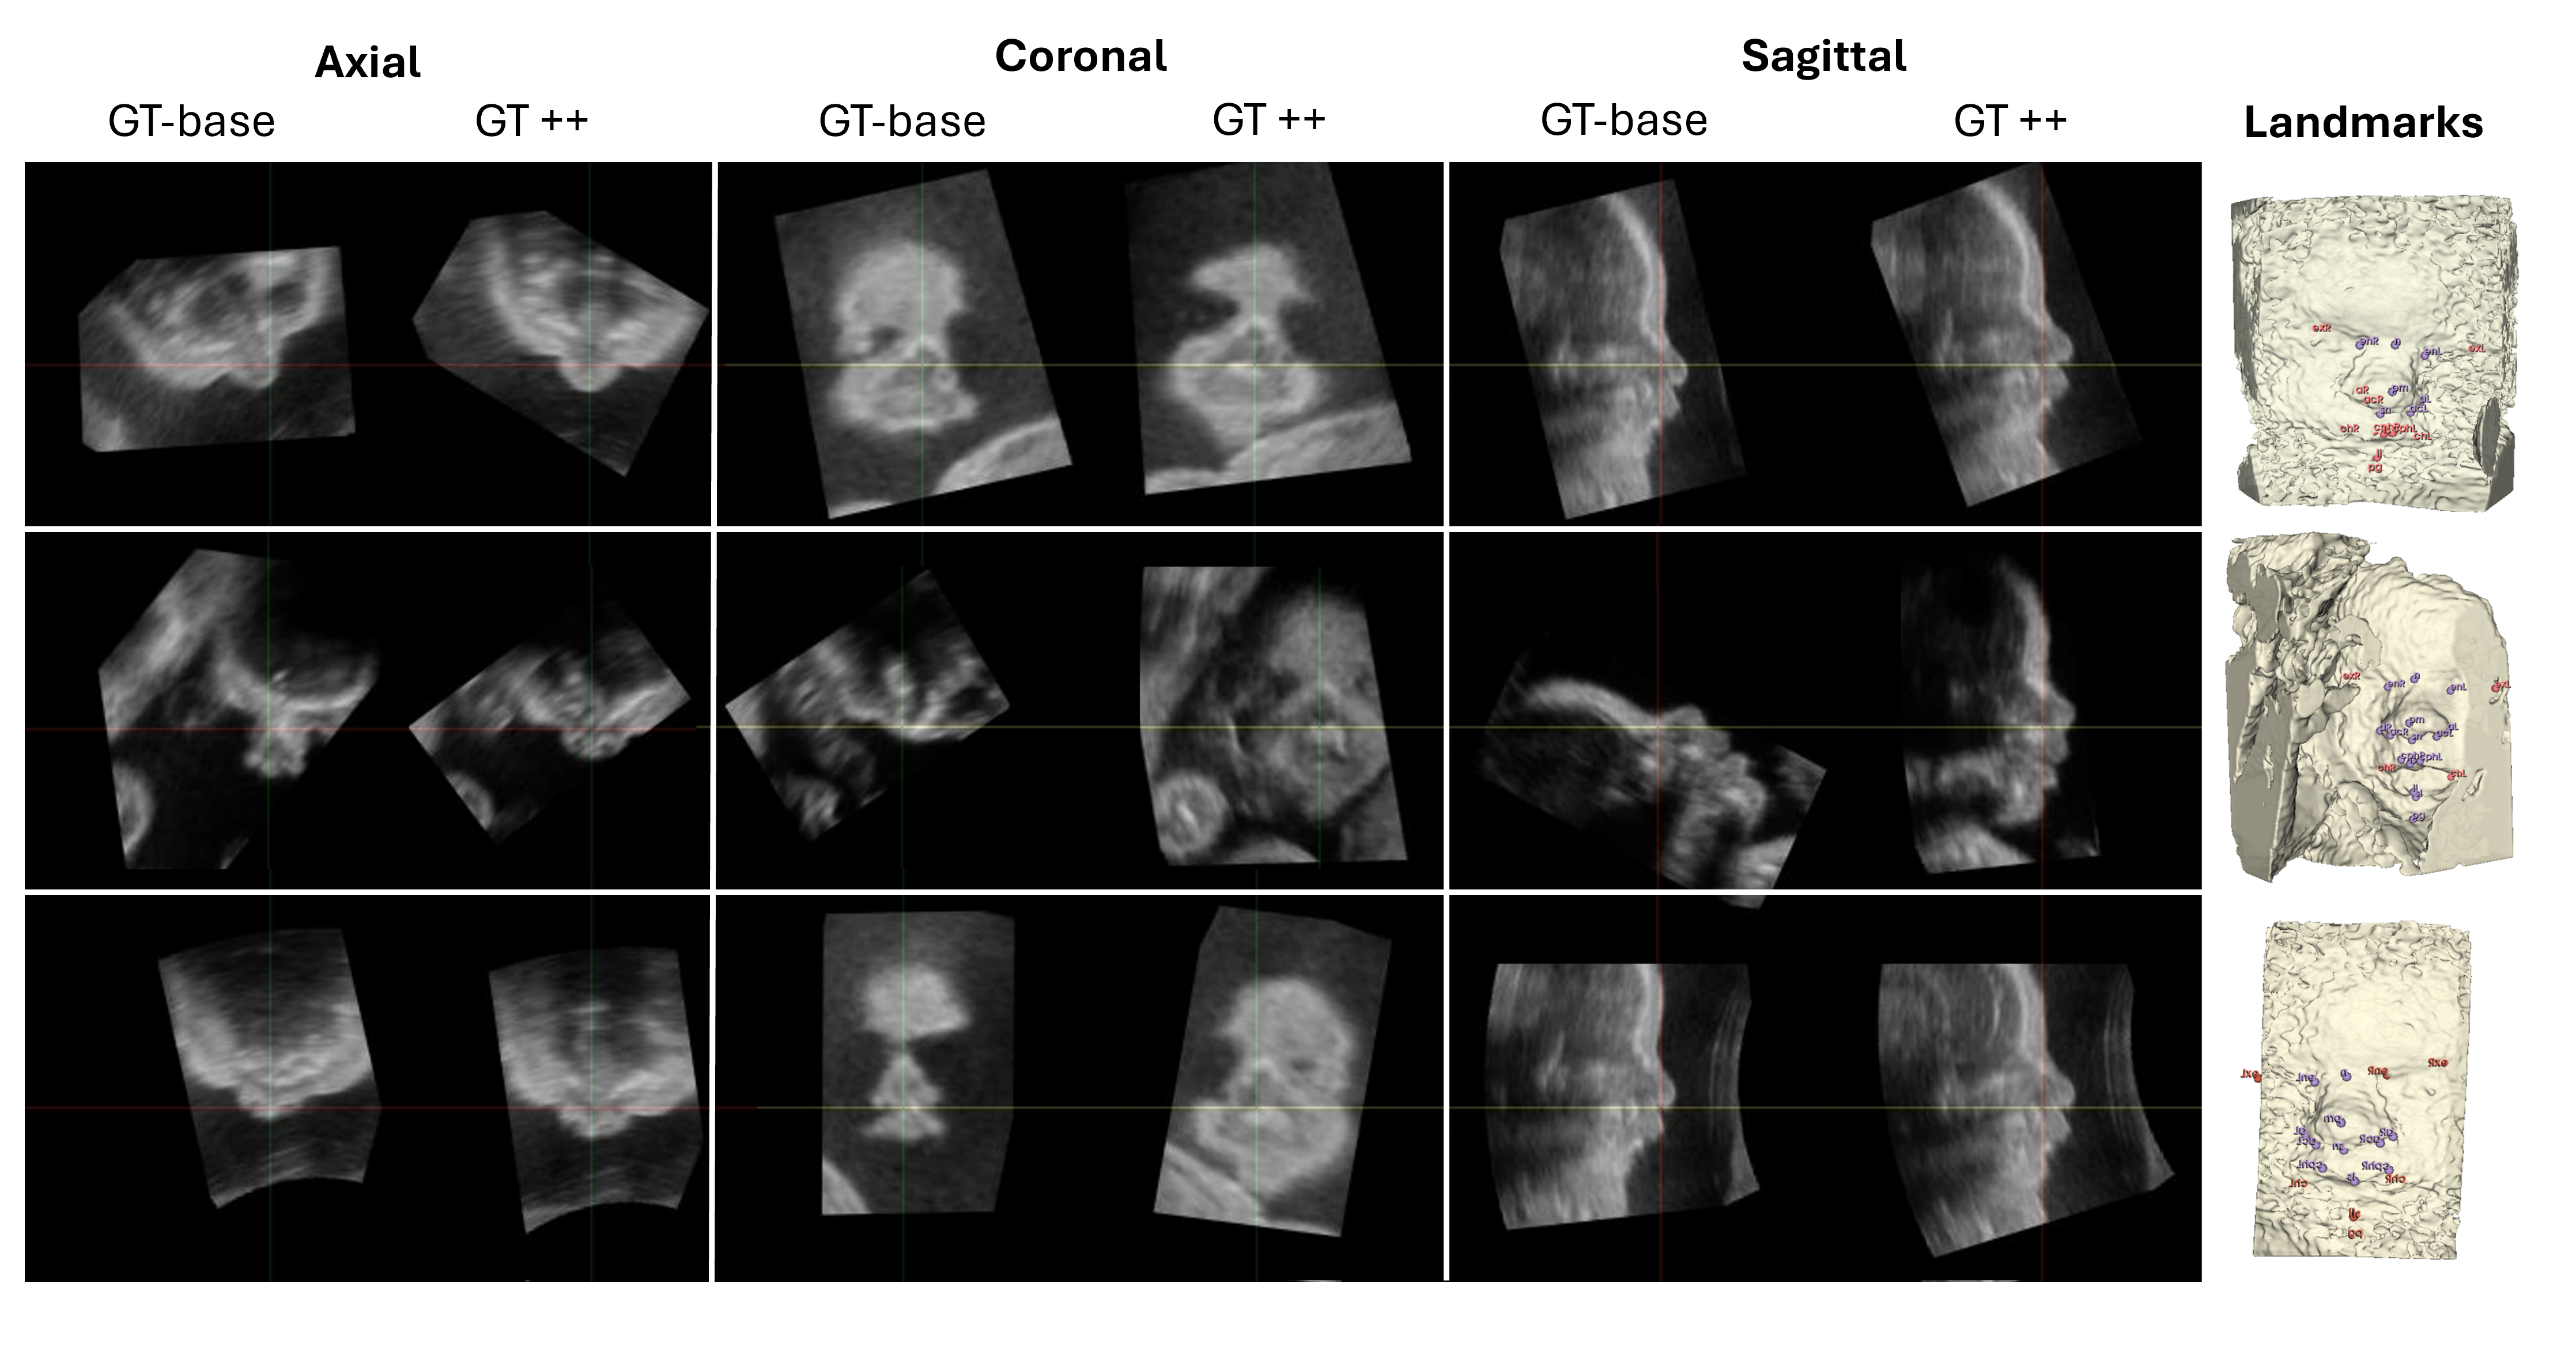

Refer to caption

Figure 3: Examples of facial planes generated using GT-base and GT++. Clinician-defined landmarks are shown in purple, while red landmarks represent those added through the completion process. Each row corresponds to a different subject. The columns display sagittal, coronal, and axial views, for both methodologies to facilitate comparison.

Figure 3 provides qualitative examples comparing GT-base and GT++ facial planes, illustrating how landmark completion leads to more accurate corrections and improvements in the predicted planes.